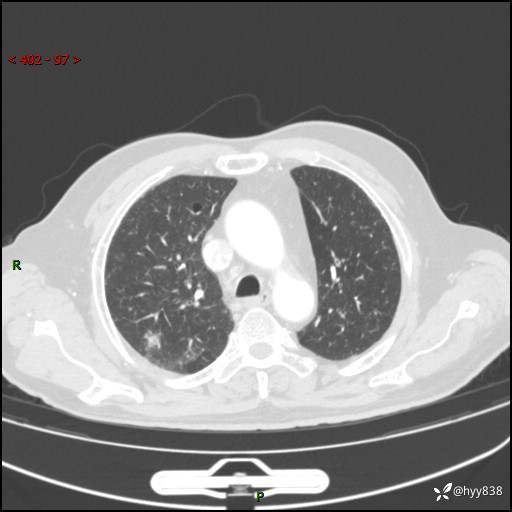

胸部CT复查(2024.7)